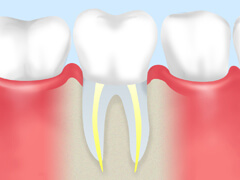

根管治療

虫歯が悪化すると、歯の奥の神経や血管は虫歯菌に冒されて死んでしまいます。そこまで進行した虫歯は、従来では抜くしか方法がありませんでした。しかし、近年では歯をできるだけ残すために根管治療(こんかんちりょう)が行われています。

根管治療とは、歯の中にある「根管」という細い管の中から、虫歯菌に冒されて死んでしまった神経や血管を取り除き、内部をきれいに洗浄・消毒して薬剤を充填する治療です。根管はとても細かく複雑に枝分かれしているため、この治療は簡単ではありません。しかし、確実に行えれば歯を残すことができるのです。

歯とはすべてそろってこそ正しく機能するものであり、もし1本で失うと歯並びや咬み合わせが乱れる原因にもなります。歯をできるだけ残し、お口の健康を維持することが根管治療の目的だといえるのです。